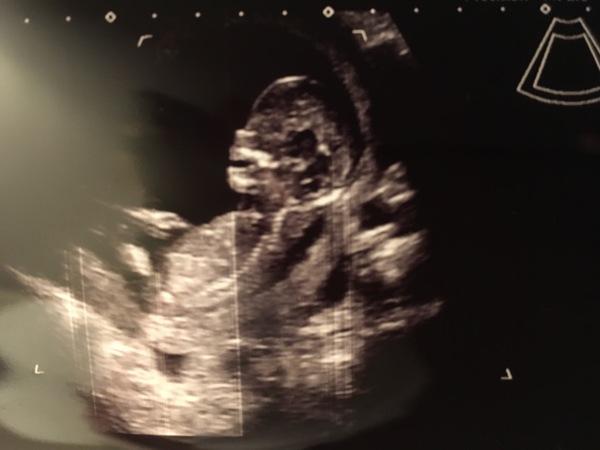

Hello all, checked no in after my dating scan today. I am 13+1, as the measurements have confirmed.

They found a heartbeat, but couldn't get the baby moving! It was sleeping on its side

I had to go to the courtyard and jump around for ten minutes (not looking weird at all!), then they rescanned: this time, the baby had turned onto its back, but was still asleep... It woke up eventually to make some jerky whole-body movements and to open its mouth a few times.